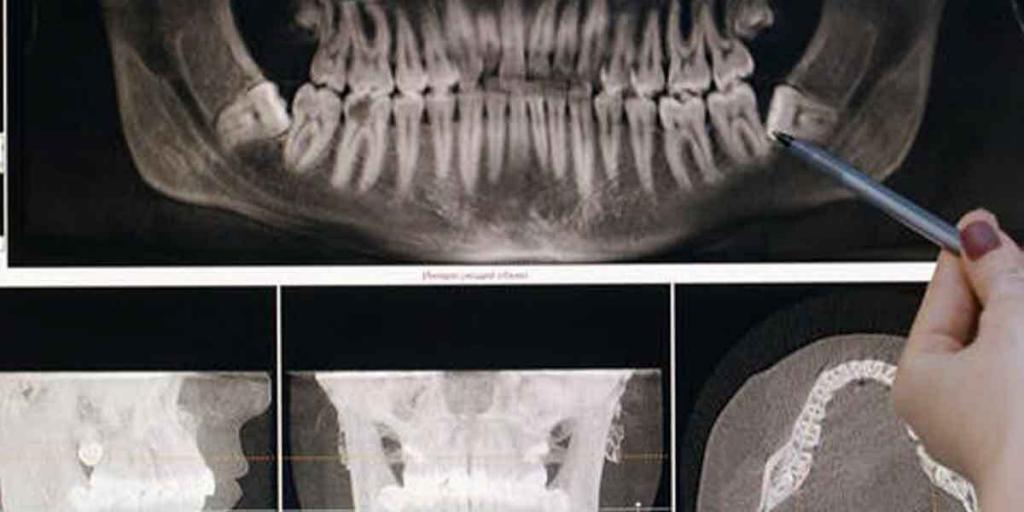

Different Types of Dental X-Rays Performed and Role of The Dentist

Getting an x-ray is a common role of the dentist. But what are dental x-rays, and why do you need them? Dental x-rays allow your dentist to see inside your mouth, check for tooth decay or damage that cannot be seen during a regular exam. Besides, they can find cavities before they become painful. Thus, […]